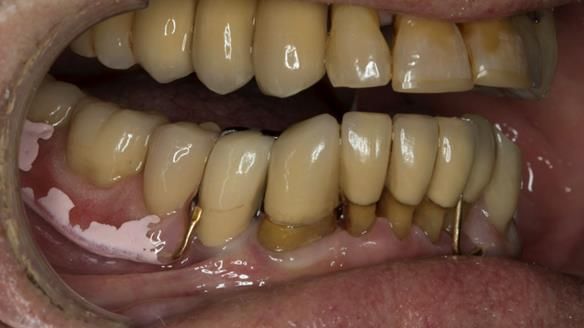

An honest note on the impressions

It’s important to say that I struggled considerably to obtain accurate impressions of Ken’s lower anterior teeth. This was a difficult situation and not one that went smoothly.

At one stage, a tray became locked in position and had to be sectioned and removed carefully. This is not something I like but it does happen, particularly in cases with long, thin teeth and compromised anatomy.

This case was always about function, not aesthetics.

Ken’s teeth were never going to look perfect.

There were stained composites, old restorations, and obvious wear.

That was accepted from the outset.

The way Rowan lengthened the teeth — particularly in the upper RPD — to match the existing gingival recession on the remaining teeth was superb. The dentures sit naturally within the context of the rest of the mouth.